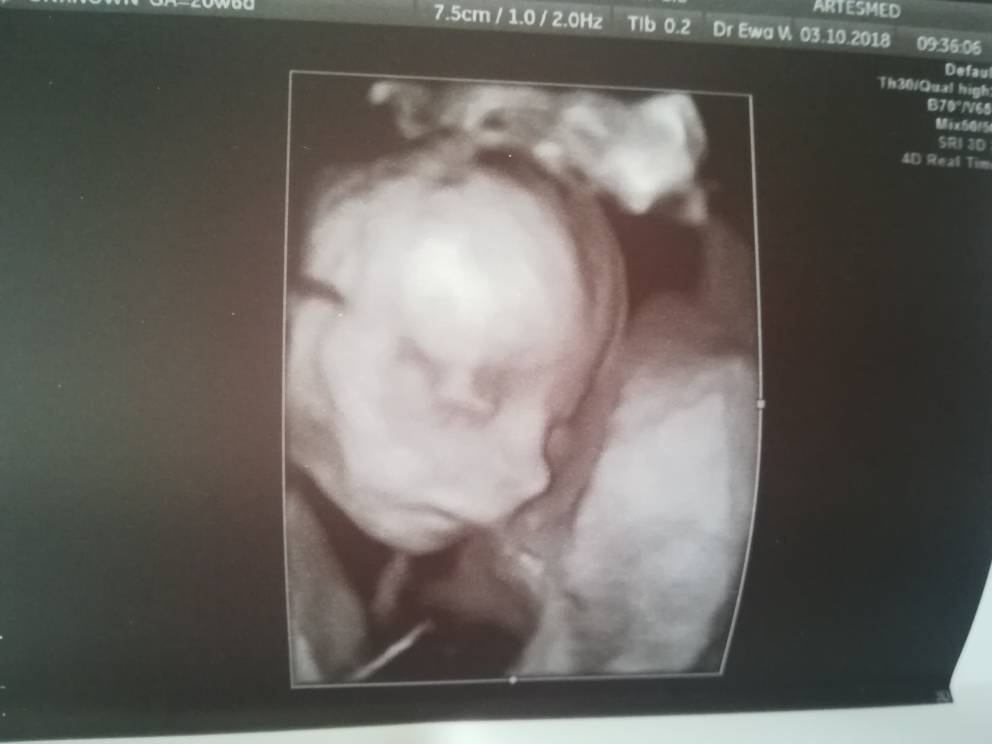

Wszystko dobrze, zdrowa dziewucha. Całe 460 g szczęścia :)

Mihasia gratuluję zdrowej dziewczynki :)

Mihasia gratuluję zdrowej dziewczynki :) Zobacz załącznik 904060

Tobie również gratuluję zdrowej kobietki. Jest fantastyczna [emoji7]